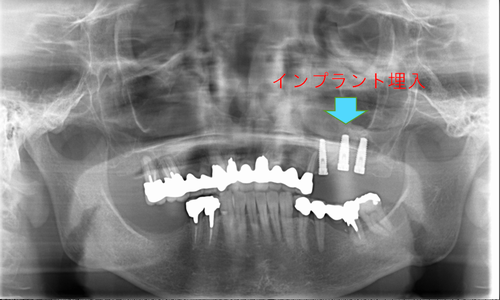

この患者様は、右上の奥歯の歯茎から出血してくるとのことで来院されました。歯周組織検査とレントゲンで診断を行った結果、重度の歯槽膿漏が認められ、保存不可能の為、抜歯になると伝えたところ、入れ歯は絶対に嫌だと言われたので、インプラント治療となりました。CT撮影を行ったところ、上顎洞底までの距離が3ミリ程度しかなかったのですが、骨が固く、フィクスチャーの一次固定が良好だったので、開窓法による上顎洞底挙上術とフィクスチャーの埋入を同時に行いました。約10カ月後に二次手術を行い、上部構造をセットしました。また、右下の臼歯部のブリッジにも大きな二次カリエスが認められ、7番の遠心根が抜歯になり、6番、7番にインプラント治療をしました。